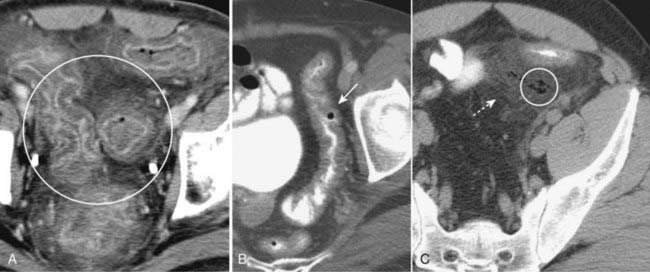

Figure 18-10 Key findings on CT of the GI tract.

Findings applicable to any part of the bowel and key to the diagnosis of bowel abnormalities on CT. A, There is thickening and enhancement of the wall of the bowel (circle). When distended, as these loops of large bowel are, the bowel wall is normally very thin. B, There is submucosal infiltration of the wall (thumbprinting) (solid white arrow). In this case of ischemic colitis, it most likely represents edema with some hemorrhage. C, Infiltration of the surrounding fat is seen (dotted white arrow), a sentinel finding that usually heralds adjacent inflammation. There is also extraluminal air (circle), a sign of bowel perforation.

imageThere are several important findings common to any part of the bowel, which are key to the diagnosis of bowel abnormalities by CT.

image Thickening of the bowel wall. The normal small bowel lumen does not exceed about 2.5 cm in diameter, and the wall is usually no thicker than 3 mm. The colonic wall does not exceed 3 mm with the lumen distended.

image Submucosal edema or hemorrhage. Submucosal infiltration produces varying degrees of thumbprinting, nodular indentations into the bowel lumen representing focal areas of submucosal infiltration by edema, hemorrhage, inflammatory cells, tumor (lymphoma), or amyloid.

image Hazy or strandlike infiltration of the surrounding fat. Extension of inflammatory reaction outside of the bowel into the adjacent fat is a sentinel finding that heralds associated disease (Fig. 18-10).

image Extraluminal contrast or extraluminal air. Indicates the presence of a bowel perforation (Fig. 18-11).